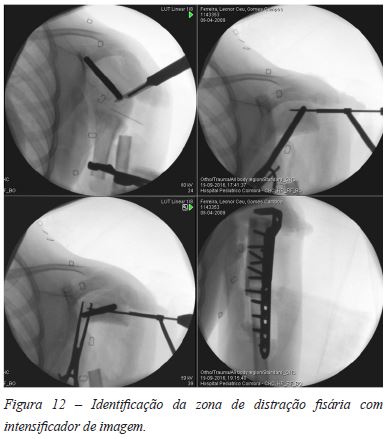

Realizou-se osteotomia na zona marcada (Figura 10), com desinserção sequencial do tricípite e restantes músculos posteriores do braço, com margem de segurança. De seguida foi aplicado novo cravo a nível da epífise, constatando-se com manipulação suave que estava completa a epifisiolise proximal na zona medial do úmero proximal (Figura 11). Com apoio de intensificador de imagem identificou-se a zona de distração fisária com palpação com agulha, procedendo à incisão circunferencial da cápsula com bisturi nessa zona de distração fisária (Figura 12).